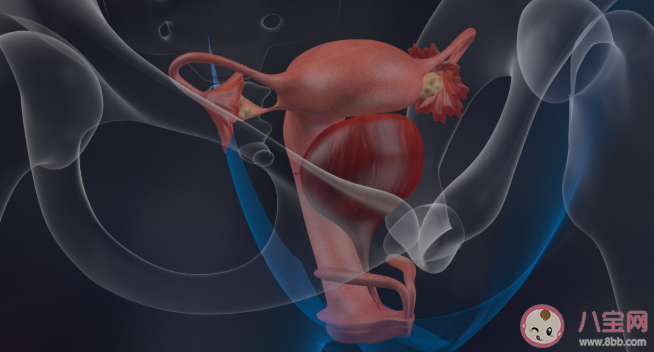

當卵巢釋放出卵子后,我們的輸卵管會拾取卵子,讓其在輸卵管傘端和精子結合成受精卵。

可見,一條暢通無阻的輸卵管,在成功懷孕的過程中占據著舉足輕重的地位。

可是,當輸卵管發生病變或異常的時候,就會影響輸卵管的功能,造成女性不孕的發生。